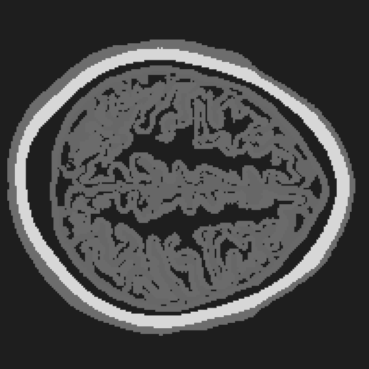

Figure 7: Stacked TRA Image with (a) Partial-transducer dataset and (b) Full-transducer dataset

To evaluate performance, we construct two acquisition setups using the same horizontal 2D slice of the phantom: (i) an idealized full-transducer dataset (Figure 3(b)) providing near-uniform coverage along the head contour, and (ii) a partial-transducer dataset (Figure 6) designed to reflect practical acquisition constraints. In the partial setup, a linear array with 51-element is repositioned around the head; for each view, the central element transmits and all other 50 elements receive. The partial setup includes 50 sweeps covering the full 360, meaning that for each sweep, the source and receivers rotate by 360/50=7.2360/50=7.2^{\circ}. Sweeping 50 views yields, per 2D slice, a channel tensor of shape (T,Ns,Nr)=(5001,50,50)(T,N_{s},N_{r})=(5001,50,50). The key distinction between these two datasets is their aperture: full-transducer provides near 360 coverage in a single placement, whereas partial-transducer attains coverage by aggregating neastest 50 receivers in a single placement, which is only around 36. Particularly, the partial-transducer setup includes only 50 sweeps, while the full-transducer setup uses all receivers covering the entire brain, with each transducer acting as a source in turn while the others serve as receivers. Compared to the full-transducer, the partial-transducer achieves coverage by combining a much smaller number of views. For each sweep, we generate the forward wavefield g(𝐱,t|𝐠){{g}}(\mathbf{x},t|\mathbf{g}) and the back-propagated wavefield p~(𝐱,t|𝐠)\tilde{{p}}(\mathbf{x},t|\mathbf{g}) and generate the TRA fragment with Eq. (7) (example in Figure 6). With the physical TRA method, the TRA fragment can be stacked to give the stacked TRA image. To validate the differences between the two datasets, we generated stacked TRA images using both datasets, as shown in Figure 7. As shown in Figure 7(b), the full-transducer dataset provides significantly greater detail in internal structures. Despite higher levels of noise and artifacts caused by the limited number of views, the partial-transducer dataset is still capable of capturing some meaningful tissue structures.